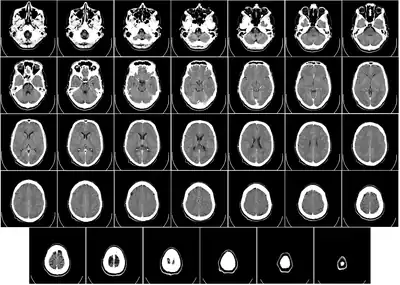

Head

CT scanning of the head is typically used to detect infarction (stroke), tumors, calcifications, haemorrhage, and bone trauma.[32] Of the above, hypodense (dark) structures can indicate edema and infarction, hyperdense (bright) structures indicate calcifications and haemorrhage and bone trauma can be seen as disjunction in bone windows. Tumors can be detected by the swelling and anatomical distortion they cause, or by surrounding edema. CT scanning of the head is also used in CT-guided stereotactic surgery and radiosurgery for treatment of intracranial tumors, arteriovenous malformations, and other surgically treatable conditions using a device known as the N-localizer.[33][34][35][36][37][38]

Two-dimensional CT images are conventionally rendered so that the view is as though looking up at it from the patient's feet.[97] Hence, the left side of the image is to the patient's right and vice versa, while anterior in the image also is the patient's anterior and vice versa. This left-right interchange corresponds to the view that physicians generally have in reality when positioned in front of patients.[98]